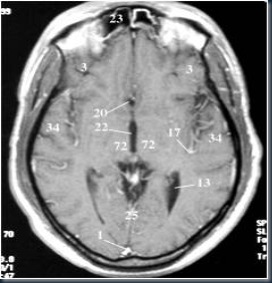

3. Potongan Axial Otak MRI

Keterangan gambar:

1. Sinus Sagital sup.

3. Lobus Frontal

4. Lobus Parietal

13. Ventrikel Lateral

16. Corpus Callosum

17. A. Serebri Media

20. Foramen Monro

22. Ventrikel III

23. Sinus Frontal

31. Aqueduct Serebri

43. Arteri Basiler

|

44. Ventrikel IV

45. Cerebellum

48. Pons

50. Sinus Sphenoid

52. Medulla

55. Sinus Sigmoid

63. Lidah

67. Fornix

72. Thalamus

73. A. Meningeal